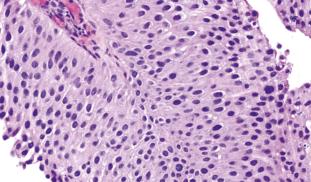

Molecular pathoepidemiology is the study of the cause and natural history of disease on a molecular, individual, and population level, utilizing tissue specimens and data from existing epidemiological studies. We aim to use this method to better diagnose bladder cancer, to more accurately estimate its risk of recurrence, and to inform personalized targeting of anti-cancer drugs. In the long term, we plan to apply these principles to other cancers and related illnesses.